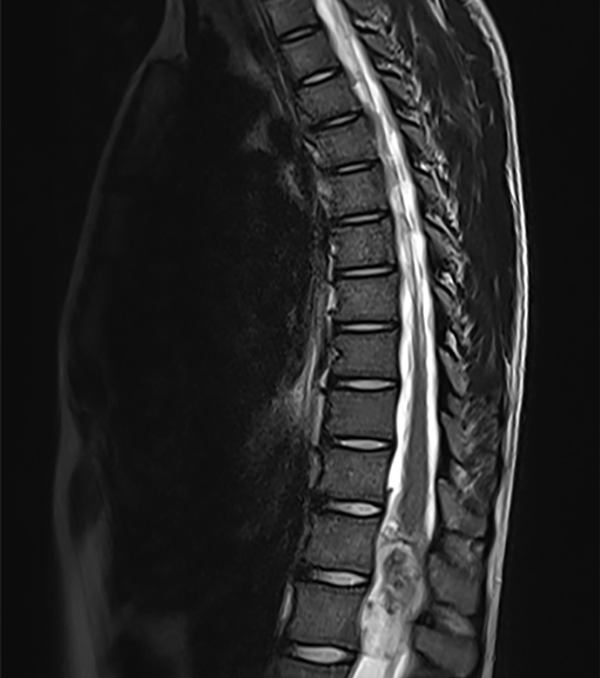

Se realizan imágenes de Resonancia Magnética (RM) de cerebro simple en donde se evidencia ligera dilatación supra e infratentorial, sin signos de paso de líquido transependimario. RM de columna total evidencia lesión nodular, expansiva, en el cono medular entre T12-L1 (18 x 20 x 53 mm) (Figura 1) que comprime las raíces de cola de caballo y el cono medular. En la region lumbosacra se evidencia una segunda imagen nodular que se localiza en la región central y distal del canal lumbar y sacro (20 x 26 x 55.5 mm) (Figura 2).

Figura 1. RM secuencia T2: Tumor intradural intramedular en cono medular T12–L1